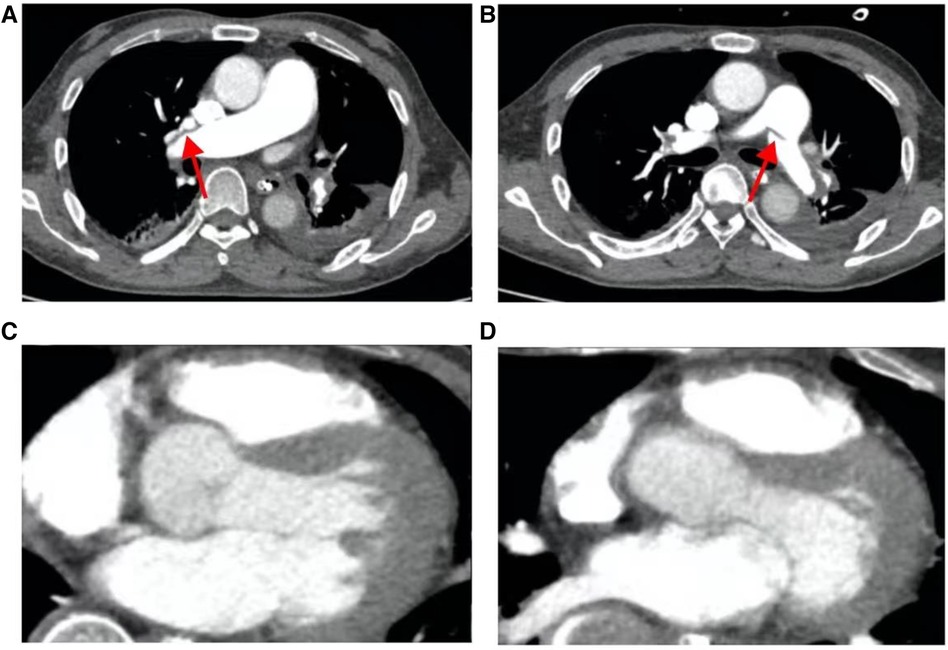

On March 28, 2023, at 14:20, the patient was transferred to our hospital's Intensive Medicine Department. The patient had a temperature of 36°C, a pulse of 98 beats/min, a respiratory rate of 20 breaths/min, and blood pressure of 92/62 mmHg (under the combined auxiliary treatment with norepinephrine, epinephrine, and dobutamine), Vasoactive Inotropic Score (VIS): 105 points. Pulse oxygen saturation (SpO2) was 99%. Blood gas analysis showed a pH of 7.49, blood oxygen concentration of 50%, carbon dioxide partial pressure of 26.00 mmHg, oxygen saturation of 99%, oxygen partial pressure of 106.00 mmHg, blood lactate level of 3.5 mmol/L, and an oxygenation index of 212.00 mmHg. The patient's laboratory test results were Creatinine 176 umol/L, D-dimer >20 mg/L, N-terminal pro-B-type natriuretic peptide (NT-proBNP) 14,535 pg/ml, and cardiac troponin I 1.12 ng/ml. The ECG results indicated a sinus rhythm, abnormal Q waves (Ⅲ, aVF), and T wave changes. Echocardiography showed a left atrial anteroposterior diameter of 26 mm, a right atrial anteroposterior diameter of 46 mm, a left ventricular end-diastolic diameter of 40 mm, a right ventricular anteroposterior diameter of 23 mm, a left ventricular ejection fraction of 54%, thrombi in both atria, severe pulmonary arterial hypertension (70 mmHg), and an atrial septal defect width of approximately 4.1 mm (Figure 2, Table 1). Thrombosis formation was seen in the bilateral popliteal veins (complete occlusion). Pulmonary artery CT angiography indicated bilateral multiple PEs and intra-atrial occupying lesions in both atria (Figure 3).

Figure 3 Pulmonary artery CT angiography results when the patient was hospitalized. (A) The red arrow points to the filling defect of the right pulmonary artery; (B) the red arrow points to the filling defect of the left pulmonary artery; (C) the red arrow points to the space in the right atrium; (D) the red arrow points to the space in the left atrium.